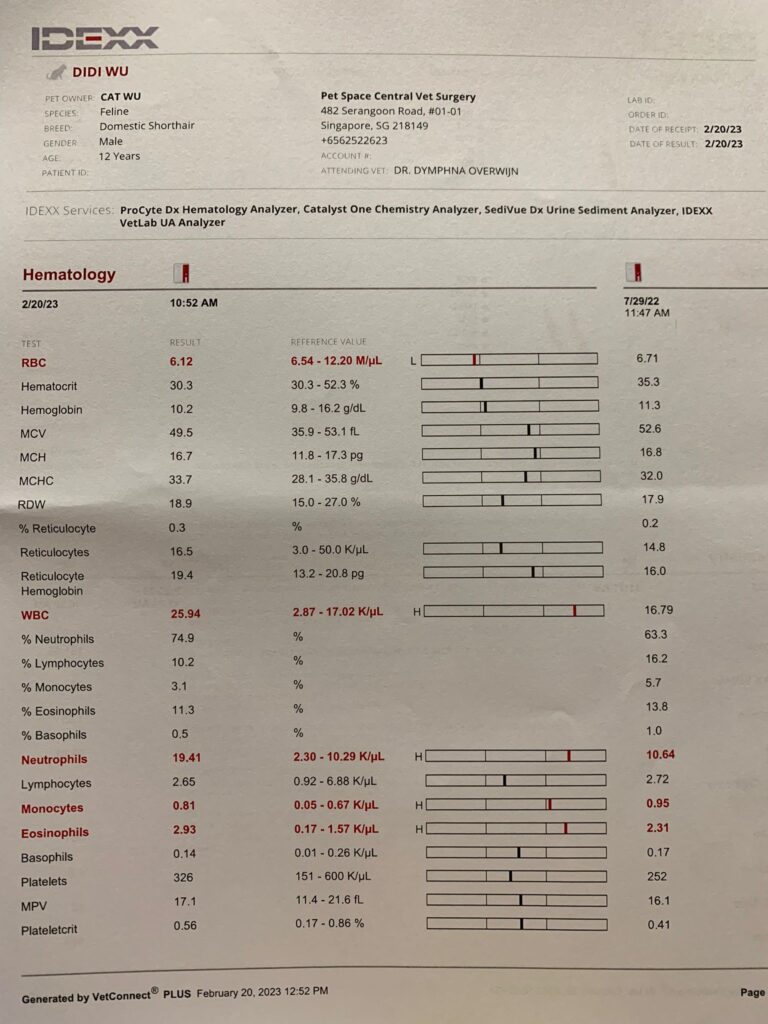

20 Feb 2023

Liver a little bit enlarge kidney ok

Bladder moderate

dr see his Jul 2022 bloods n u/s

Mouth not good, don’t look like the reason for the weight lost

Left upper gum red, so should have remnants there

3.66kg, lose 120g

Thin but strong

Taking full bloods, urine n serum n Afast see spleen for any changes. Nails cutting n ear cleaning.

Also testing glob differential to see if it can defect tumor or not.

His heart sound ok.

Sdma 19

Glob wbc producing tumor – send out to see the diff type of glob results. If one type of glob go up, then highly is tumor. If all go up then not as bad.

Sg 1.014 – Dilute urine, losing a little protein in urine, can try low dose semintra 1mg/kg (nowadays vet give 2mg per kg, n they finally acknowledge that 10-15% become anemic as a side effect)

I trying 0.5mg/ kg and review to make sure rbc stable n upc go down. UPC 0.39

U/s spleen still bad, not bigger or smaller.

and gall bladder n etc n etc forgot the details not good, can be just bacteria. But just start

0.19ml Clav.

Rbc down to 6.12, lucky HCT still 30.3%.

Wbc NEU all go up.

45mg once daily ursofalk for the gall bladder too.

Retest 3 weeks

130pm: back in 猫房 – he go 4 diff water bowls drink water. I think I need to up his Subcut frequency also. Sdma 19 also

He poo 1.5/10, w blood (dr d says may be due to stress)

Alt 283- given milk thristle he really hate it. I suddenly think of ornipural – I think first.

I’m short today I had given milk thristle, Clav and ursofalk. Didn’t give semintra yet, Tmr bring to 5G. Think Tmr I will give ornipural too.

Night: he seem ok, but really v thin.